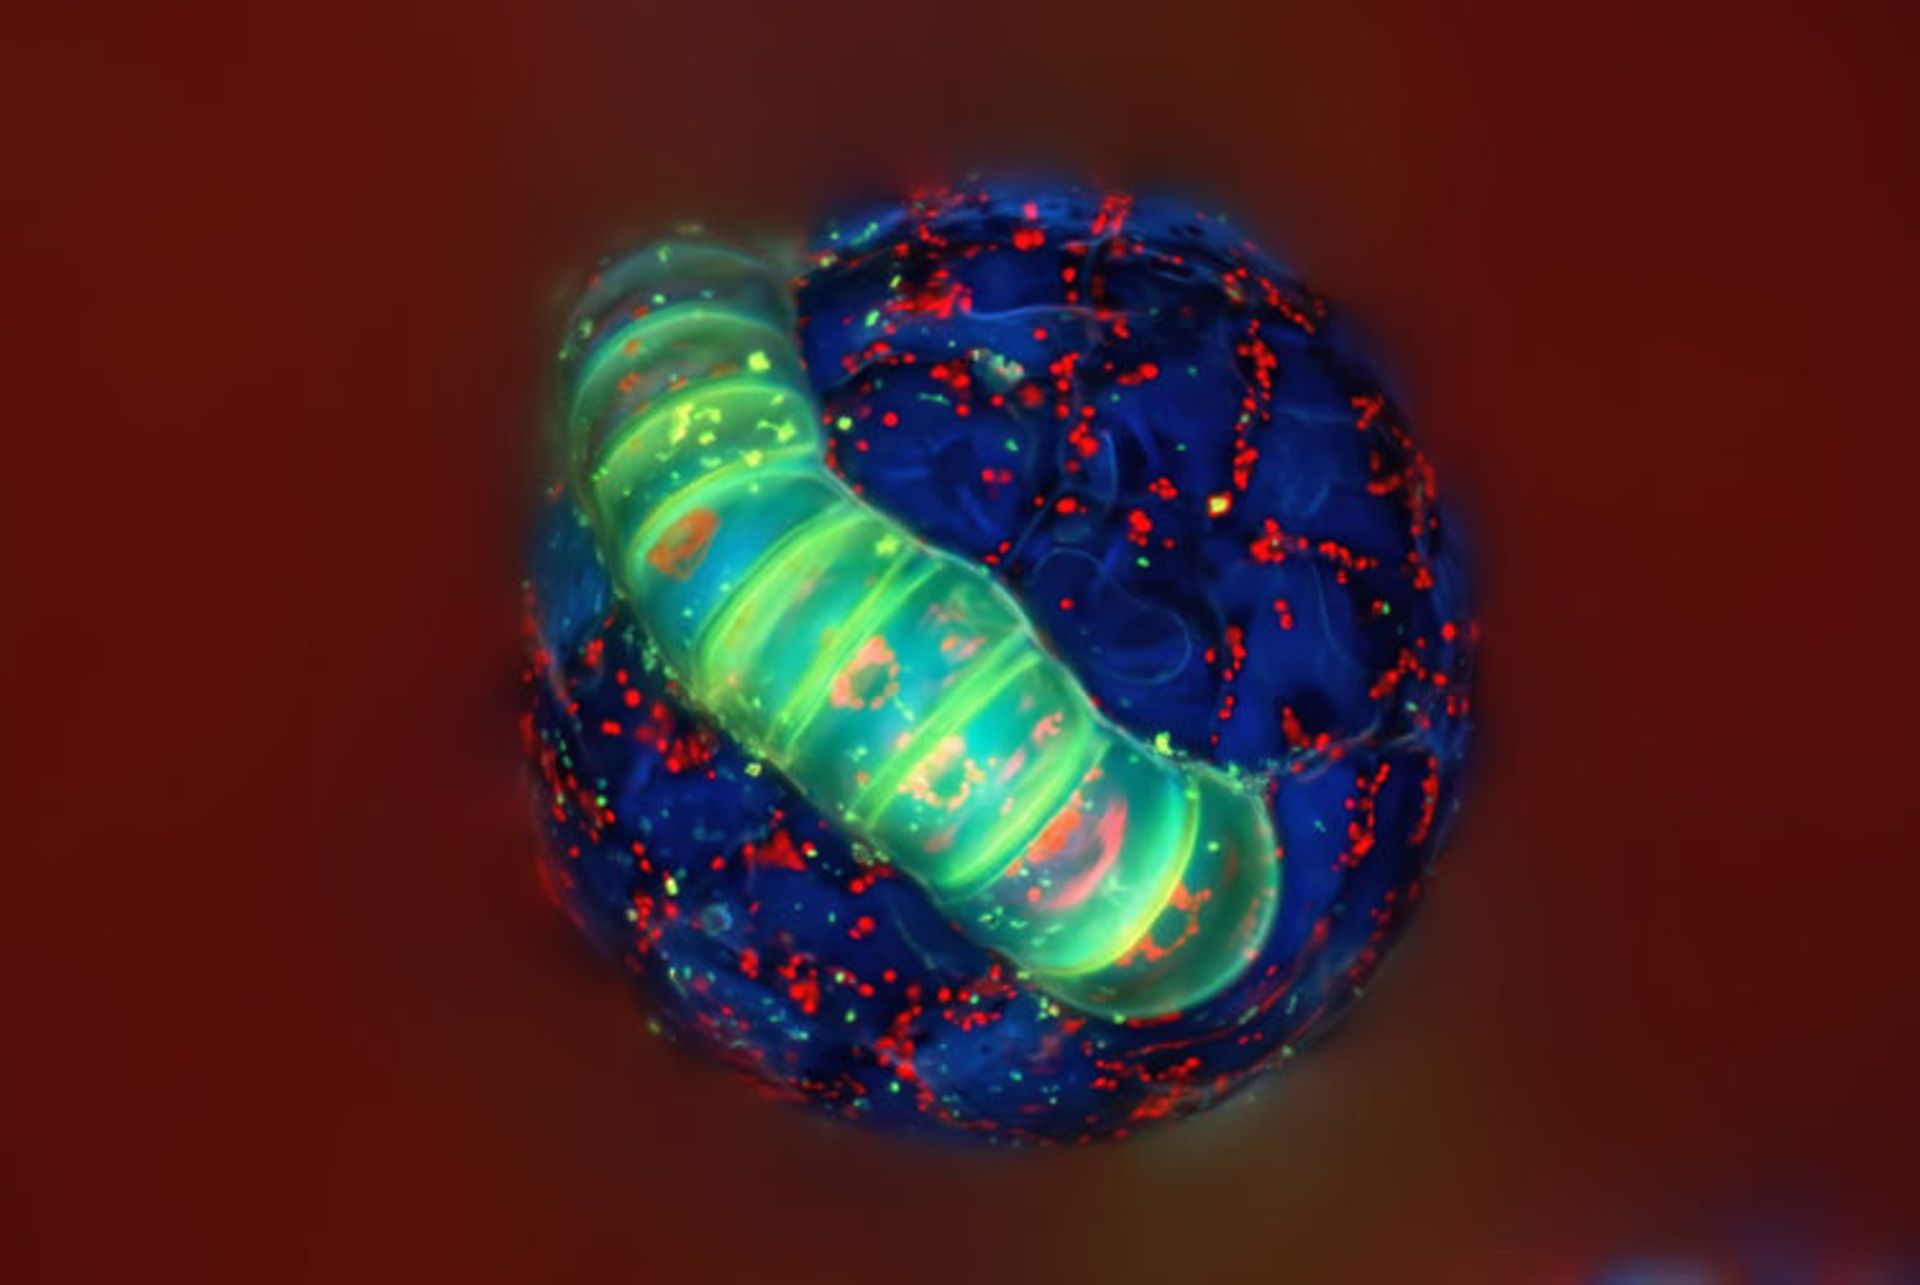

سارکومرها در یک سلول عضلانی قلب حاصل از سلول بنیادی پرتوان القایی انسان؛ بزرگنمایی ۶۰ برابری

ابیگیل ناینینگر و دکتر دیلن برنت (Abigail C. Neininger & Dr. Dylan Burnette) از آمریکا